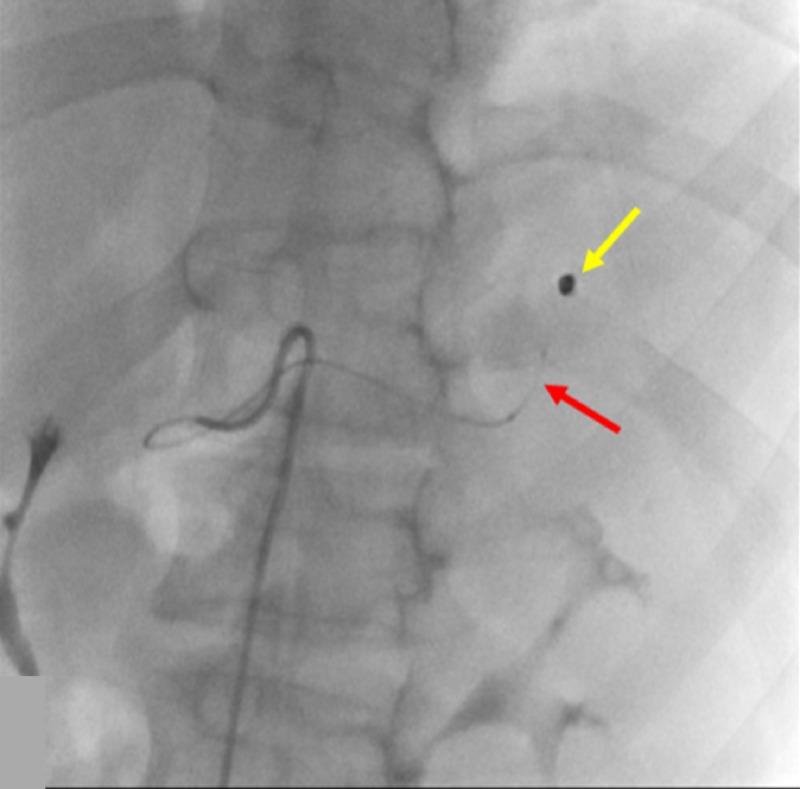

The use of traditionally available intra-arterial devices have historically been designed with the adult patient population in mind. Currently, there are not manufactured devices specifically tailored for use during pediatric interventional procedures, pressuring interventional operators to adapt commonplace and readily available devices for interventional management. Experienced interventional operators understand that pediatric and adult interventions can entail vastly different management, affecting patient care and outcomes. To address the pitfalls in pediatric interventional management, an accredited fellowship specifically for pediatric interventional radiology is available. However, devices must equally evolve with the training available in order to adequately address interventional management of the pediatric patient population. Interventional device innovation can be considered the initial step towards bridging the technical and procedural gaps necessary for refining pediatric intervention. The introduction of steerable microcatheters in interventional radiology has innovated procedural protocols, but has never been documented in pediatric patients until this time.

传统可用的动脉内装置在设计时历来考虑的是成年患者群体。目前,尚无专门为儿科介入手术设计制造的装置,这迫使介入手术操作人员采用常见且容易获得的装置进行介入治疗。经验丰富的介入手术操作人员明白,儿科和成人介入手术在管理上可能有很大差异,会影响患者护理和治疗结果。为解决儿科介入治疗管理中的缺陷,现有专门针对儿科介入放射学的认可进修项目。然而,装置必须与现有的培训同步发展,以便充分应对儿科患者群体的介入治疗管理。介入装置创新可被视为弥合完善儿科介入治疗所需的技术和程序差距的第一步。可操控微导管在介入放射学中的引入革新了手术方案,但在此之前从未有过在儿科患者中的相关记录。